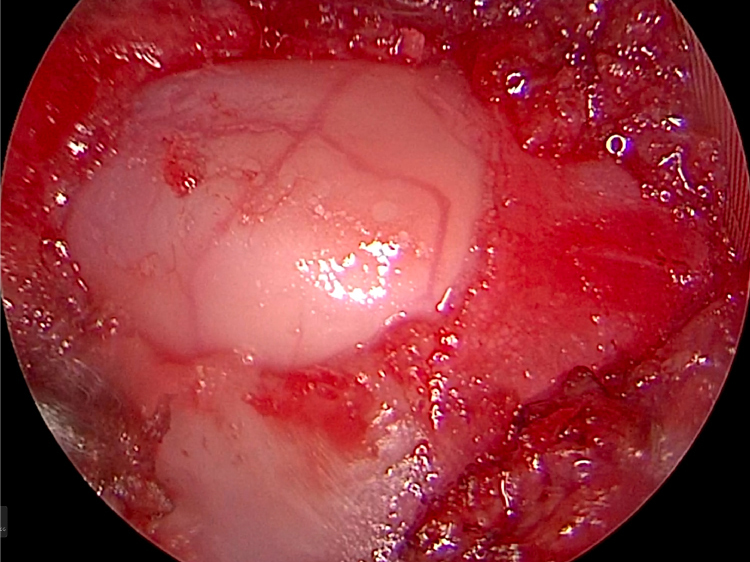

CTで責任部位を特定し小さな筒を入れ画面を見ながらアプローチしていく。必ず透視をする。

とても小さな2mmのドリル(ラウンドバー)で削っていきます。

とても繊細な手技で神経を使います。せぼねにおよそ6mmほどの穴をあけて椎間板物質をかき出していきます。